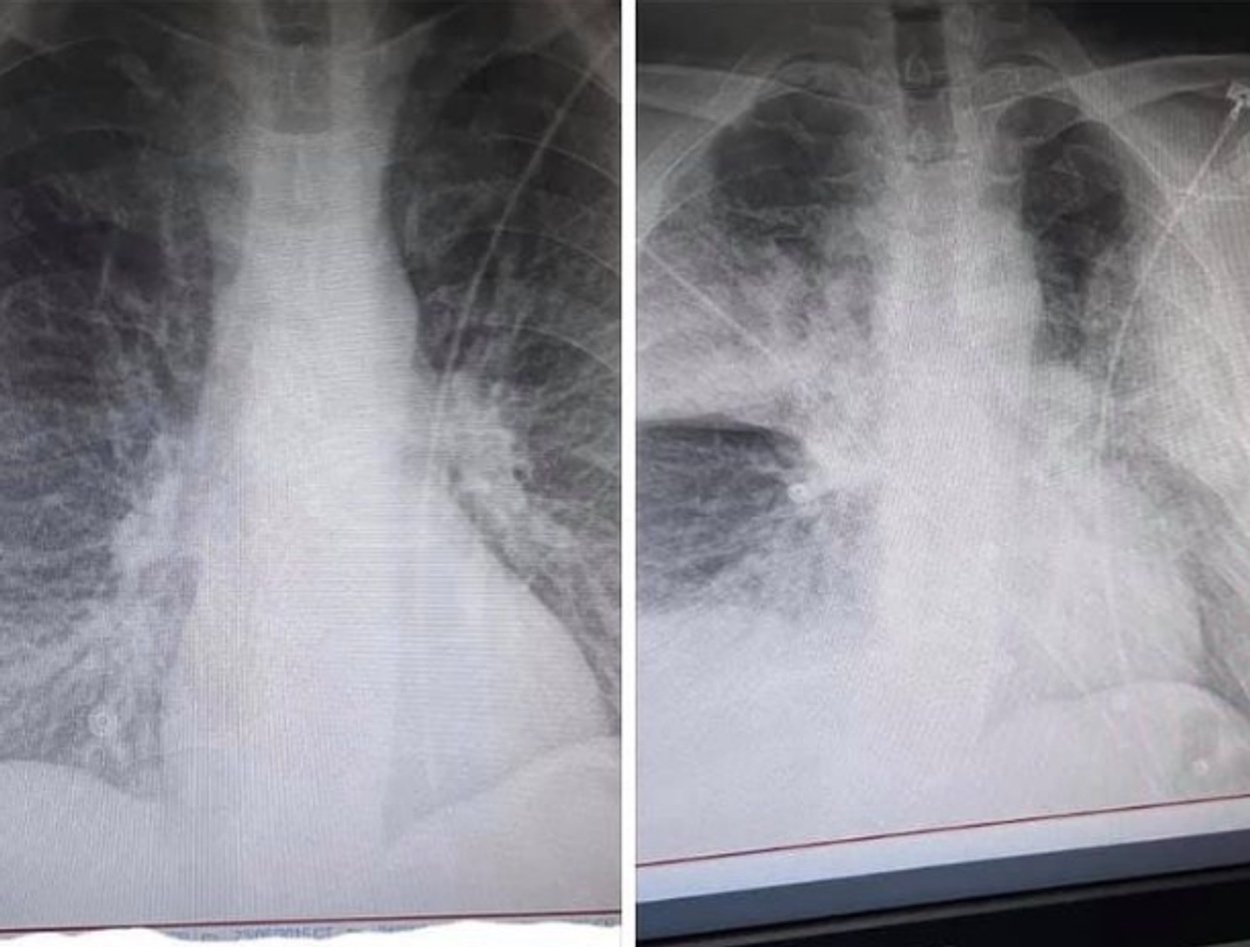

Κορονοϊός: Επίμονος και ύπουλος δολοφόνος! Μεταλλάχθηκε 4 φορές στο σώμα 45χρονου και τελικά τον σκότωσε!

Ο κορονοϊός δεν είναι ένας απλός ιός όπως θέλουν πολλοί να πιστεύουν και να νομίζουν ότι είναι άτρωτοι και αυτό το αποδεικνύει μια περίπτωση ενός 45χρονου άνδρα που δόθηκε στην δημοσιότητα από τους επιστήμονες.